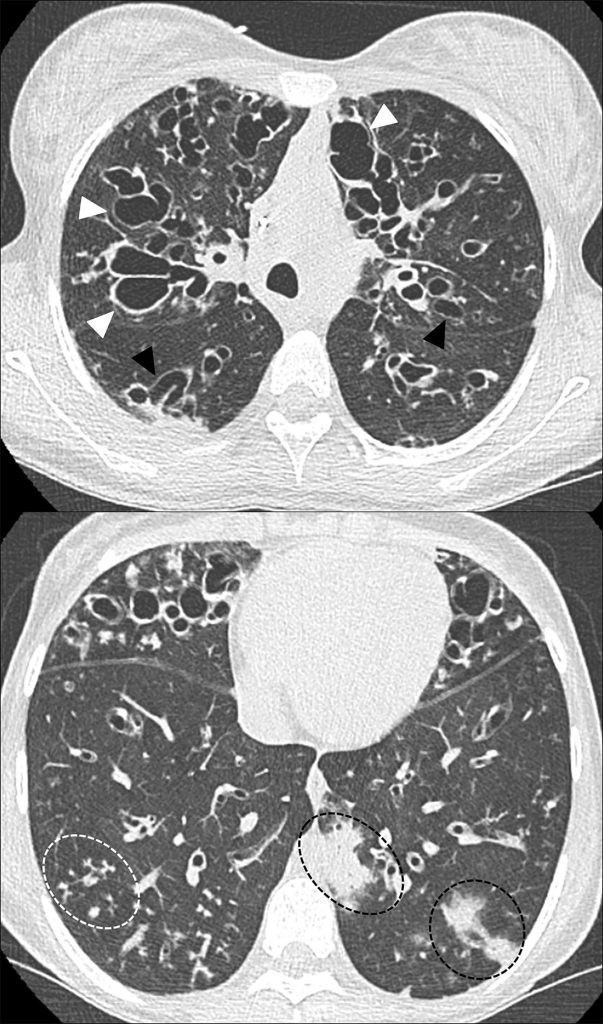

En tomodensitométrie thoracique, les bronchectasies sont plus facilement visibles ainsi que les épaississements des parois bronchiques et impactions mucoïdes proximales et distales (figure 125.2).

Fig. 125.2 Tomodensitométrie thoracique : atteinte pulmonaire sévère chez une fille de 13 ans.

Dilatation des bronches diffuses prédominant aux lobes supérieurs, kystiques (flèches blanches) et variqueuses (flèches noires), à parois épaisses. Impactions mucoïdes distales à la base droite (micronodules en « arbre en bourgeons », pointillés blancs), condensations alvéolaires témoignant d’une surinfection à la base gauche (pointillés noirs).

Source : CERF, CNEBMN, 2022.